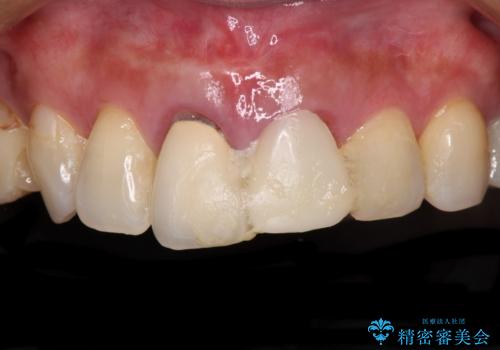

- 治療中の前歯の仮歯がひどい状態であるとのことで来院された患者様です。

治療中の前歯は根管治療の途中であり、根尖部に痛みを感じる状態でした。

まずは審美的な仮歯を装着し、根管治療を行った後にオールセラミッククラウンにて補綴治療を行うこととしました。